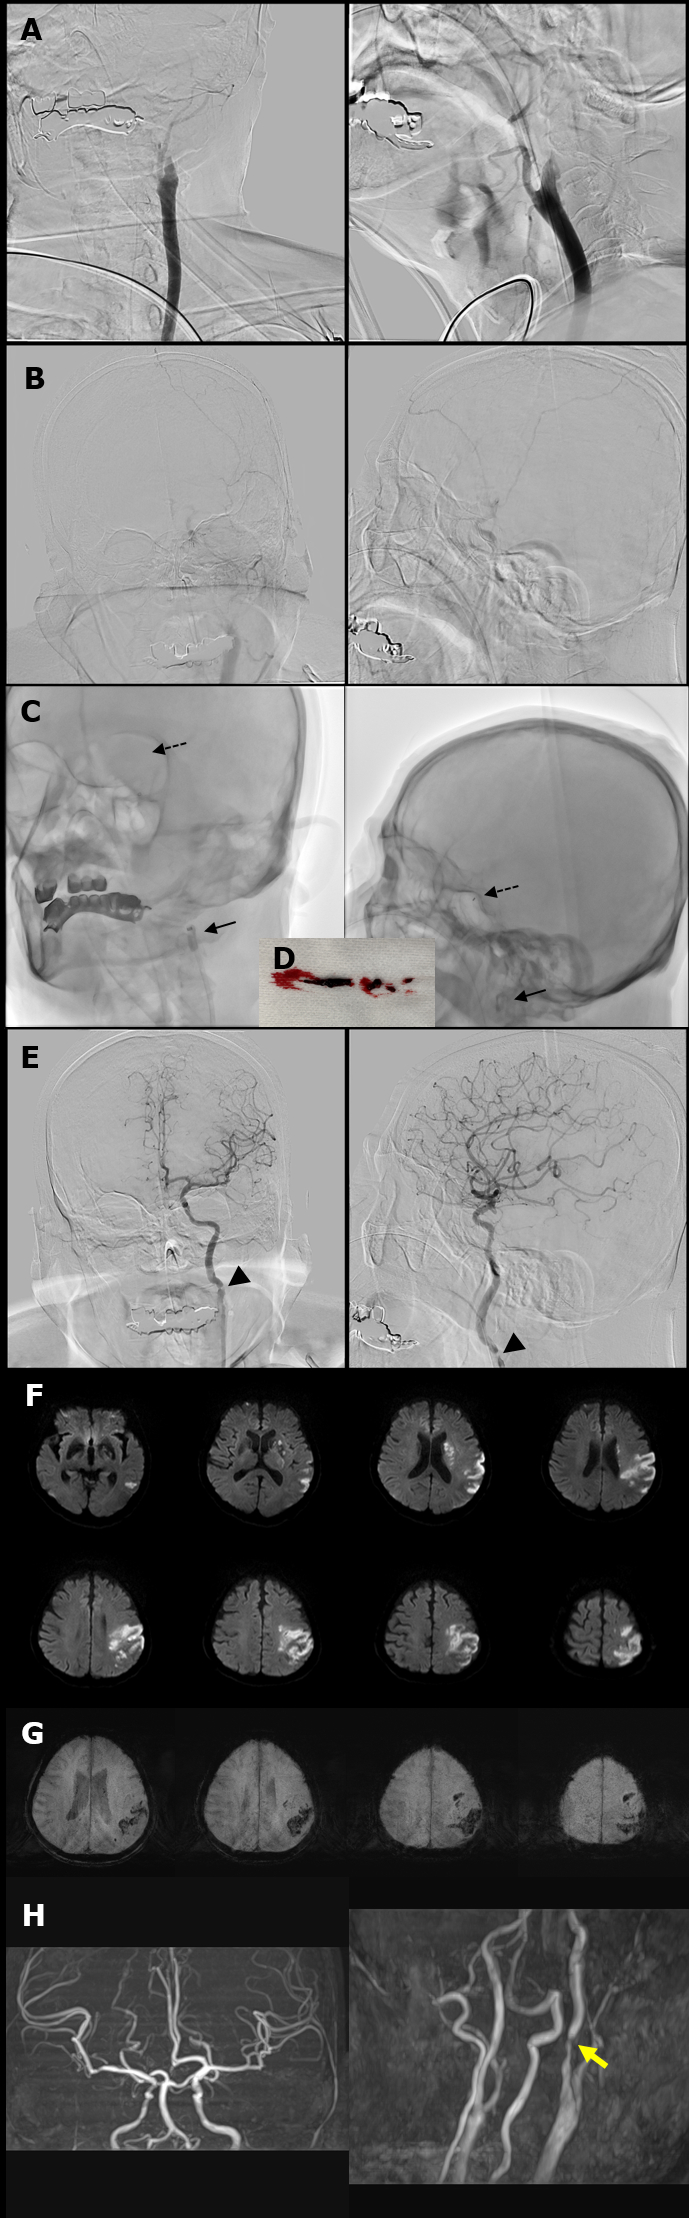

An 84-year-old male was transferred from another hospital for decreased mentality with right hemiparesis. He had visited the hospital for chest pain. While waiting for examination, he suddenly collapsed with desaturation and was transferred for proper management. Computed tomography angiography showed left proximal ICA occlusion and the left anterior cerebral artery with the left middle cerebral artery supplied via the anterior communicating artery. Electrocardiography indicated anterior wall ST elevation myocardial infarction (STEMI). Portable echocardiography findings suggested left anterior descending (LAD) artery territory insult. After a discussion with the attending cardiologist, we decided on intervention for STEMI first. After loading dual antiplatelet agents, PCI was done. After the procedure, we did EVT on the left ICA. The first pass effect was achieved by aspiration thrombectomy.